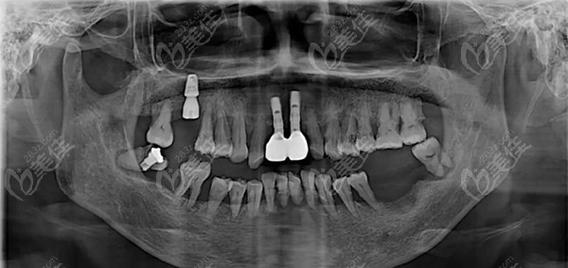

种牙前是否需要拍片,是许多准备接受种植牙手术的患者关心的问题,从临床实践来看,拍片不仅是必要的,更是保障种植牙成功和安全的关键环节,种植牙手术并非简单的“种螺丝”,而是需要通过精准的影像学检查,全面了解患者的口腔内部情况,从而制定个性化的治疗方案,避免术中损伤重要解剖结构,确保种植体能够长期稳定存在于牙槽骨中。

评估牙槽骨的质量与数量是拍片的核心目的之一,牙槽骨的高度、宽度、密度直接影响种植体的稳定性和长期成功率,缺牙后牙槽骨会逐渐萎缩,若骨量不足,可能需要植骨或上颌窦提升等额外手术;若骨密度过低(如骨质疏松严重),种植体与骨的结合效率会降低,甚至导致失败,通过影像学检查,医生可以准确测量骨量,判断是否具备直接种植的条件,或需要何种骨增量方案。

规避神经血管损伤风险至关重要,颌骨内分布着重要的神经(如下牙槽神经)和血管(如上颌窦血管),若种植体植入位置不当,可能损伤这些结构,导致下唇麻木、出血等并发症,拍片能清晰显示这些解剖结构的位置和走向,帮助医生规划种植体的植入角度、深度,确保安全区域。

排查口腔潜在病变也是拍片的重要作用,患者可能存在牙根残留、囊肿、炎症、骨化性纤维瘤等问题,这些病变若术前未被发现,可能影响种植体愈合,甚至导致手术失败,拍片能帮助医生全面评估口腔健康状况,必要时先进行治疗再进行种植。

CBCT因三维成像的优势,已成为现代种植牙术前检查的重要手段,对于上颌后牙区种植,CBCT能清晰显示上颌窦底的位置和骨壁厚度,判断是否需要上颌窦内提升或外提升;对于下颌后牙区,可精准标记下牙槽神经管的位置,避免种植体进入神经管。